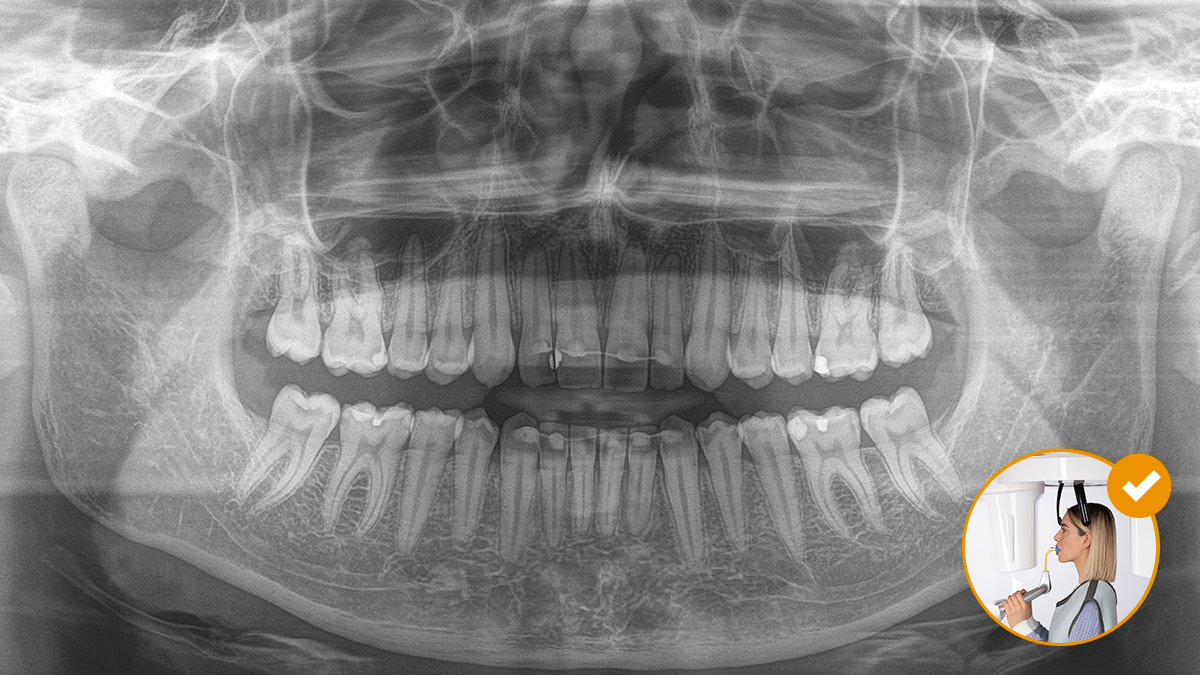

Das Ergebnis: Präzise Scans dank des Okkusalaufbisses